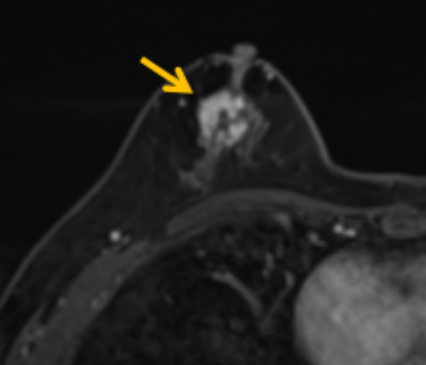

陳寶瑩評估圖像后發(fā)現(xiàn)病變?yōu)閮H僅在磁共振增強時顯示,為非腫塊樣病變,比較散,必須取得足夠多的組織才能確保病理檢查的準確性,常用的核芯針活檢獲取的組織較少,因此最終確定了磁共振引導下行真空輔助抽吸旋切活檢。取得患者及家屬認可后,陳寶瑩帶領團隊開始進行術(shù)前準備。

針對患者乳房小固定難度大這一問題,陳寶瑩通過巧妙體位和固定器的調(diào)整,順利固定好乳房。經(jīng)過磁共振多模態(tài)掃描,陳寶瑩找出病變活性成分相對集中區(qū)域,精準確定穿刺路徑,置入引導針、旋切針,到位后多角度旋切取出足量組織,拔除旋切針后即時行磁共振掃描,精準取得組織且術(shù)區(qū)出血很少,遂加壓包扎,整個過程非常順利,旋切活檢后患者回家休息。兩天后隨訪,李女士沒有任何不適,五天后皮膚上幾毫米的小切口已經(jīng)愈合。最終病理結(jié)果證實為乳腺導管原位癌,為早期乳腺癌,為患者后續(xù)針對性治療奠定了基礎。